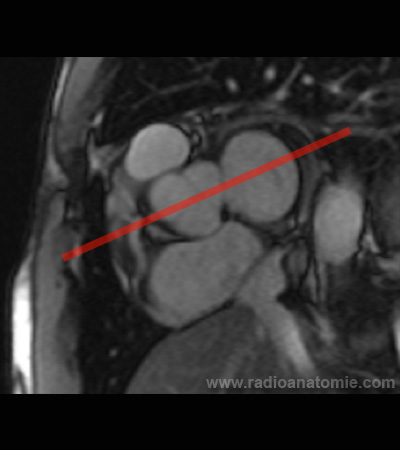

Radioanatomie et plans de coupe en IRM cardiaque

Plan 4 cavités